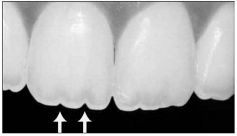

Observe a imagem a seguir:

Fonte: VIEIRA, GLAUCO F. Atlas de Anatomia dos dentes permanentes.

2 ª ed. São Paulo: Ed. Santos, 2013, 129p

Os sulcos de desenvolvimento resultam na fusão de três lóbulos. Na fusão dos lóbulos, a borda incisai apresenta um aspecto serrilhado, formando uma figura denominada Flor-de-lis. Esses lóbulos têm diferentes tamanhos. Em relação à ordem de tamanho no sentido mesiodistal, está correta a seguinte sequência